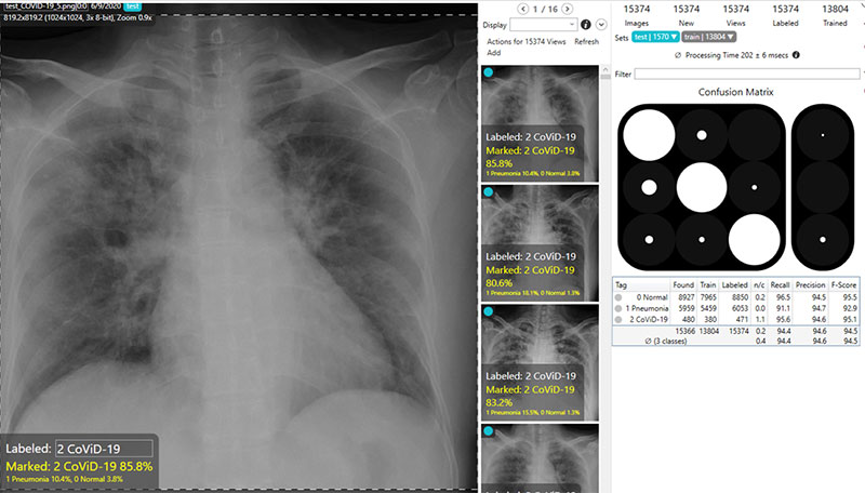

一项称为F分数的测量对于深度学习系统的整体准确性进行了评估,该系统尝试准确地预测数字图像上的图案和异常。康耐视的研究人员分析了COVID-Net数据集中的近14,000张X光片图像。这些图像被分为以下三种类型:正常、非COVID-19肺炎和COVID-19肺炎。

正如下面的表格中对多个深度学习软件包进行的比较所示,COVID-Net产生了准确的预测结果,正常图像为92.6%,COVID-19肺炎图像为94.7%。VisionPro Deep Learning软件的效果甚至更佳,正常X光片图像为95.6%,COVID-19肺炎X光片图片为97.0%。